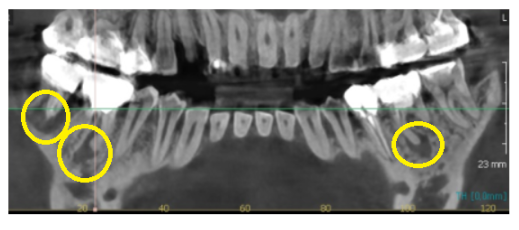

231204

좀 더 잘보이는 ct 사진입니다.

뼈는 하얗게 채워져 있어야하는데

염증이 있다보니 뼈를 녹이고

까맣게 보이네요~

치아는 잇몸뼈가 붙잡아주고 있는데

뼈가 녹으면서 잡는 부분이 없어서

들썩들썩하셨을 거예요.

그러니 씹을 때마다 욱신욱신

어디인지는 모르겠지만

좋지 않은 느낌을 받으셨을 겁니다.